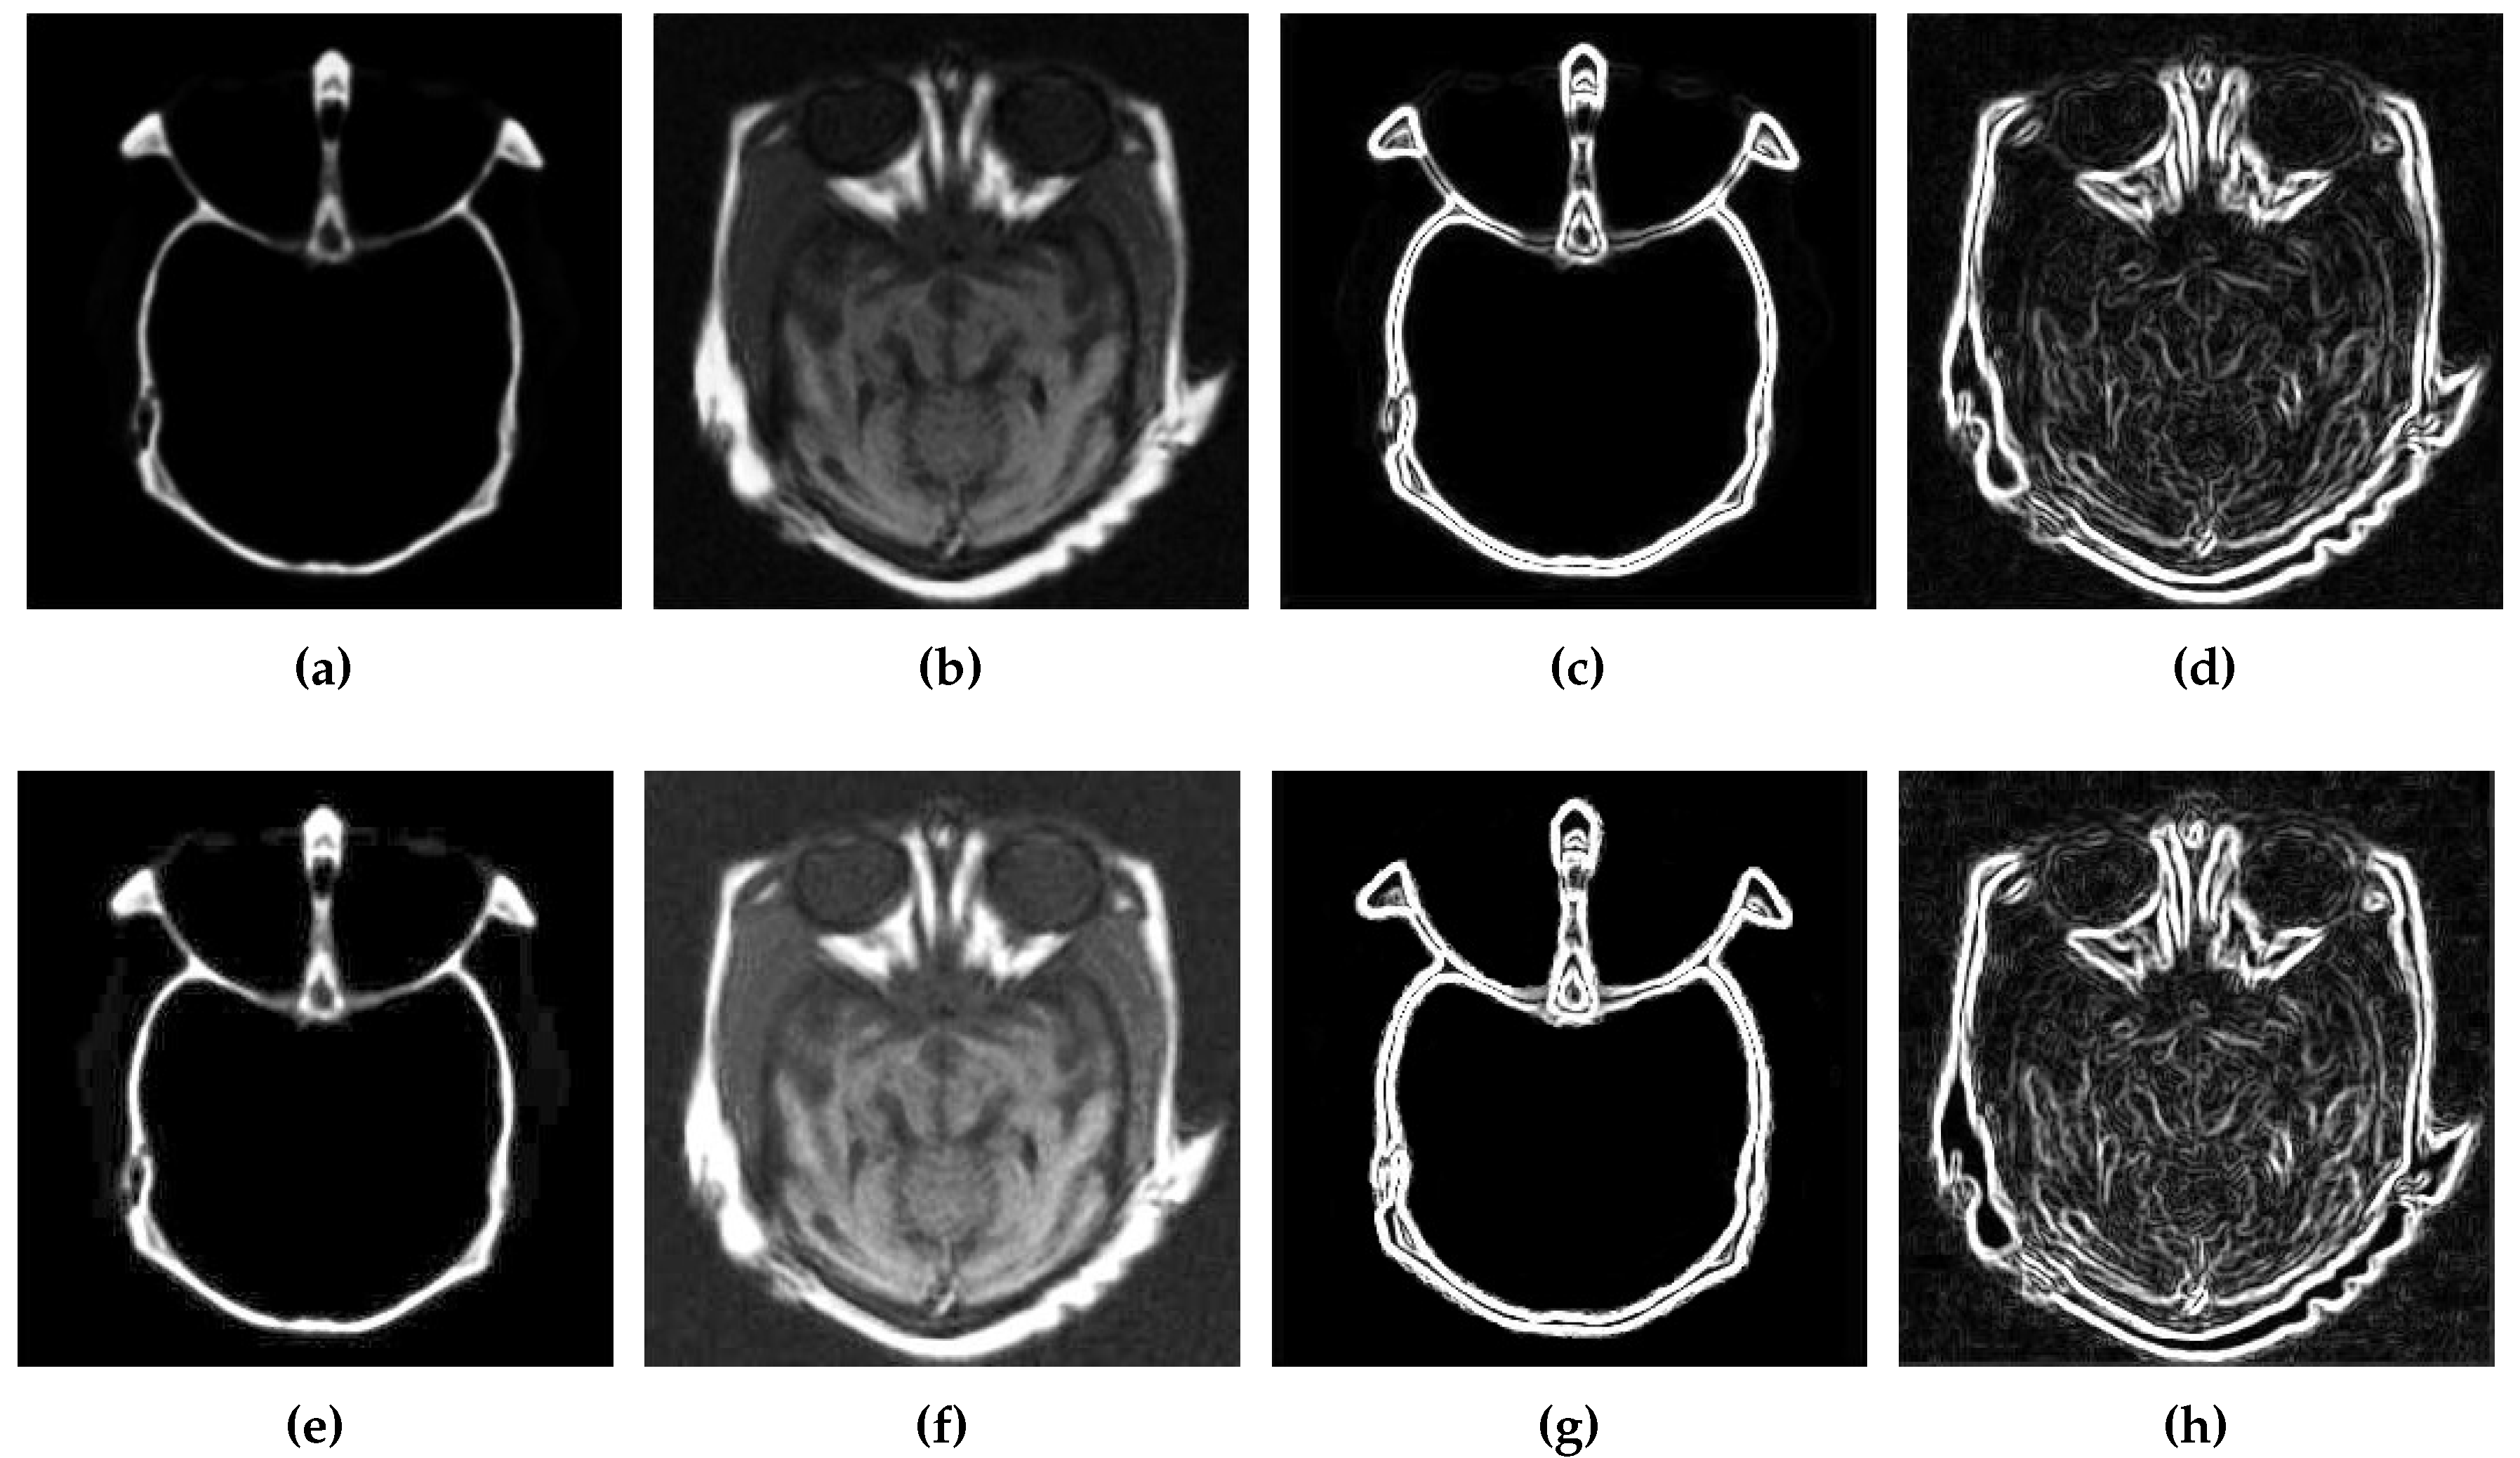

5.2.1. Qualitative Analysis of the Given Set of Algorithms for Multimodal Fusion